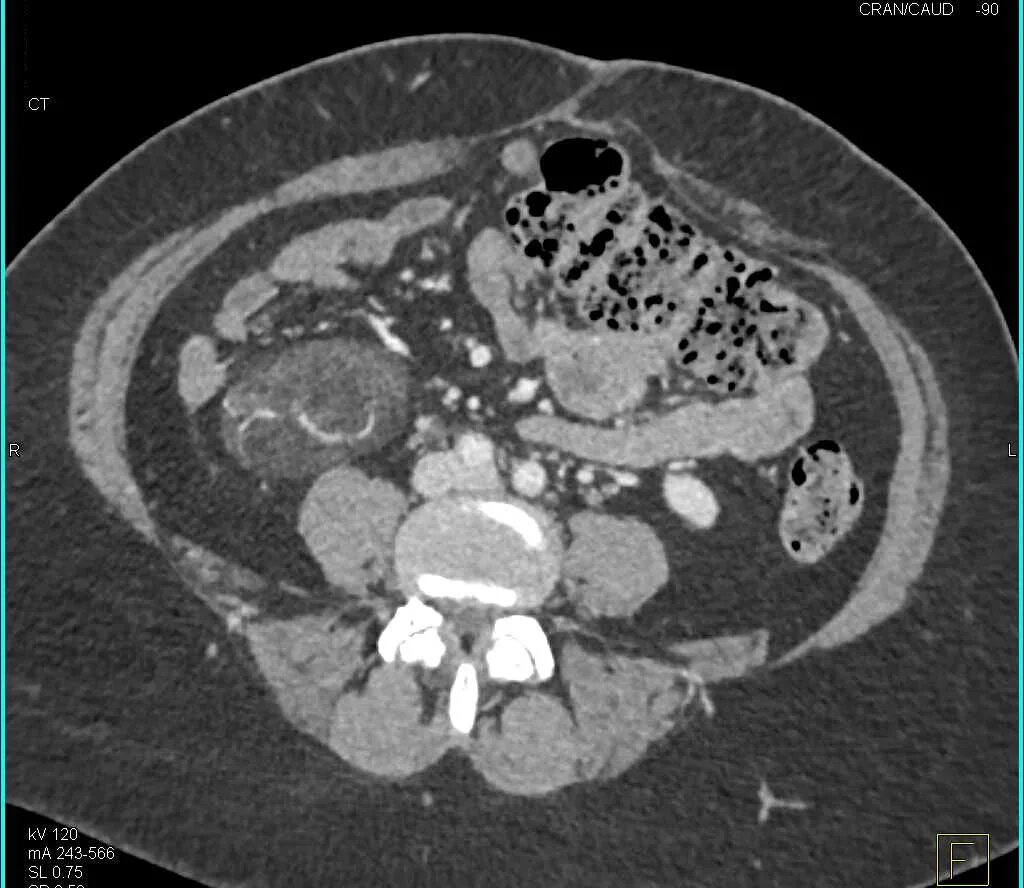

Забрюшинная онкология